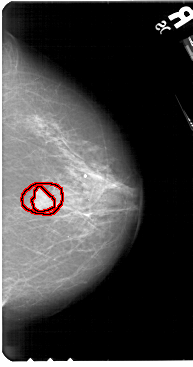

A_1574_1.LEFT_CC

LEFT_CC LINES 5491 PIXELS_PER_LINE 3256 BITS_PER_PIXEL 12 RESOLUTION 43.5 NON_OVERLAY

FILE: A_1574_1.RIGHT_MLO.OVERLAY

TOTAL_ABNORMALITIES 1

ABNORMALITY 1

LESION_TYPE MASS SHAPE IRREGULAR MARGINS ILL_DEFINED

ASSESSMENT 5

SUBTLETY 5

PATHOLOGY MALIGNANT

TOTAL_OUTLINES 2

BOUNDARY

CORE